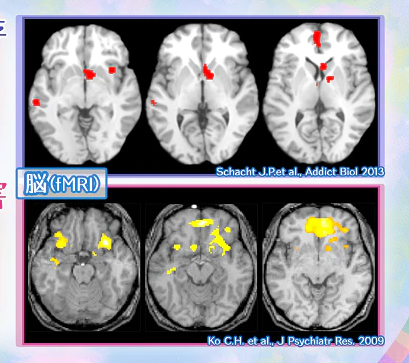

根據醫療數據,長期檢查患者腦部結構,可以發現沉癮者帶來心理與生理影響之外,確實在腦部的結構發生異變,出現了居家自閉症的傾向,而院長認為這種趨勢比酒精中毒更需受到重視。